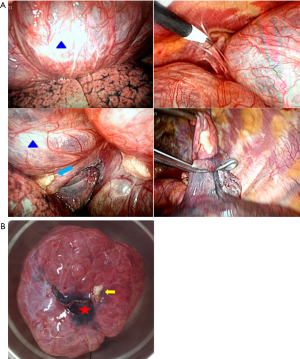

Through the video-assisted thoracic surgery (VATS) with left-sided, two-port technique was used to gain to the thoracic cavity. The giant bulla was located at the dorsal segment of lower lobe presents as a about 16-cm-sized single giant emphysematous bulla, majority compression of the left upper lobe, the multiple pleural adhesions and a nodule was a base of 1.5 cm arose from the giant bulla wall showing grayish-white, protruding, rigid and clear boundary were identified (Figure 2A).

The bulla was not collapsed even by differential lung ventilation, so the walls of the bulla were punctured. The giant bulla and the nodule were successful thoracoscopic pulmonary wedge resected with two 45 mm Ethicon linear stapling devices (Johnson & Johnson, USA) the staple line was set in the normal lung tissue along the bases of the bulla (Figure 2A). After surgical removal of bulla and nodule (Figure 2B), the compressed left upper lobe was re-expanded by manual ventilation without difficulty and one chest-tube was inserted.